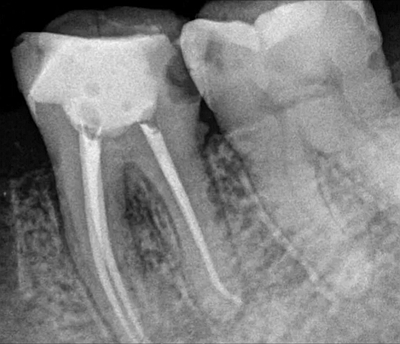

根管充填技術(shù)

1.側(cè)方加壓技術(shù)。充填前按照根管工作長(zhǎng)度和所預(yù)備的根管大小,選擇一個(gè)合適的主牙膠尖進(jìn)行充填。

2.垂直加壓技術(shù),將比工作長(zhǎng)度短一毫米的主牙膠尖插入根管內(nèi),用熱攜帶器將根管內(nèi)牙膠軟化,垂直加壓直到充填完成。

3.熱塑牙膠充填技術(shù),充填時(shí)先將牙膠加熱到所需的溫度,將針頭插入根管至距根尖3~5毫米,先向根尖部擠入少量牙膠,用垂直加壓器壓緊,再繼續(xù)將根管充滿為止。